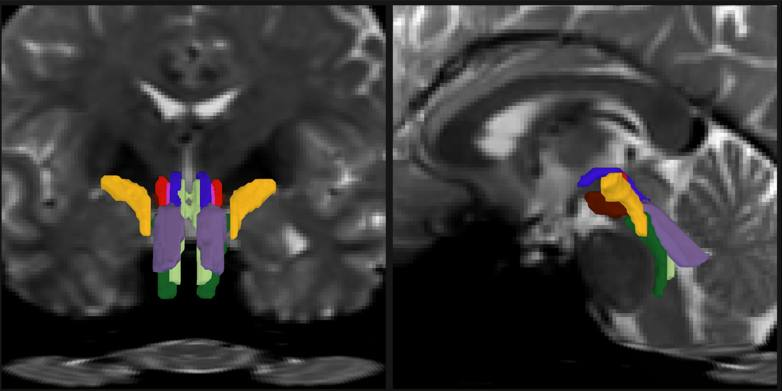

В мире нейробиологии произошел значительный прорыв: команда ученых из MIT, Гарвардского университета и Массачусетской больницы общего профиля представила программное обеспечение, использующее ИИ для автоматической сегментации восьми различных пучков нервных волокон в стволе мозга. Этот инструмент, названный BrainStem Bundle Tool (BSBT), был разработан для улучшения визуализации и анализа белого вещества мозга, что может оказать огромное влияние на диагностику заболеваний, таких как болезнь Паркинсона, рассеянный склероз и травматические повреждения мозга.

Ствол мозга играет ключевую роль в регуляции жизненно важных функций организма, таких как дыхание, сердечный ритм и сознание. Однако до недавнего времени исследователи сталкивались с трудностями в его визуализации из-за сложности структуры и наличия движений, вызванных дыханием и сердцебиением. Новый алгоритм BSBT позволяет преодолеть эти препятствия, создавая вероятностную карту волокон, что значительно улучшает понимание организации белого вещества и его изменений при различных заболеваниях.